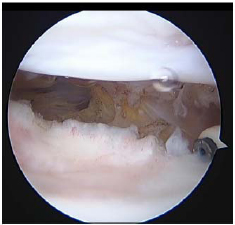

All the patients were placed in the supine position on an operating table. A tourniquet was applied to the thigh with the knee in the maximum possible flexion position to minimize capture of the quadriceps femoris muscle. The procedure was performed using the three-portal technique with two standard anterolateral and anteromedial portals in addition to the accessory superolateral portal [8, 9]. Tissue adhesions were identified (Fig. 1) and debrided using a radiofrequency device (Arthrocare, Arthrocare Sports Medicine, USA) (Fig. 2). Subsequently, gentle manipulation was performed by applying slight pressure on the tibial tubercle to avoid fractures or disruption of the extensor mechanism. After the operation, continuous passive motion was immediately initiated.